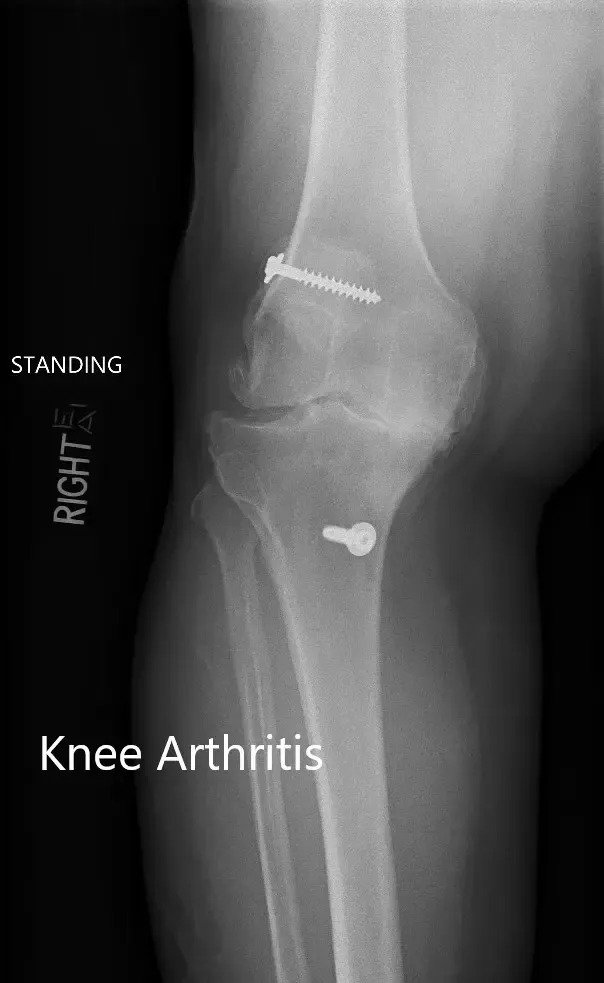

Radiografía preoperatoria que muestra las vistas AP y laterales de la rodilla derecha con tornillos retenidos, consistentes con la reconstrucción del LCA.

Radiografía preoperatoria que muestra las vistas AP y laterales de la rodilla derecha con tornillos retenidos, consistentes con la reconstrucción del LCA (imagen 3)